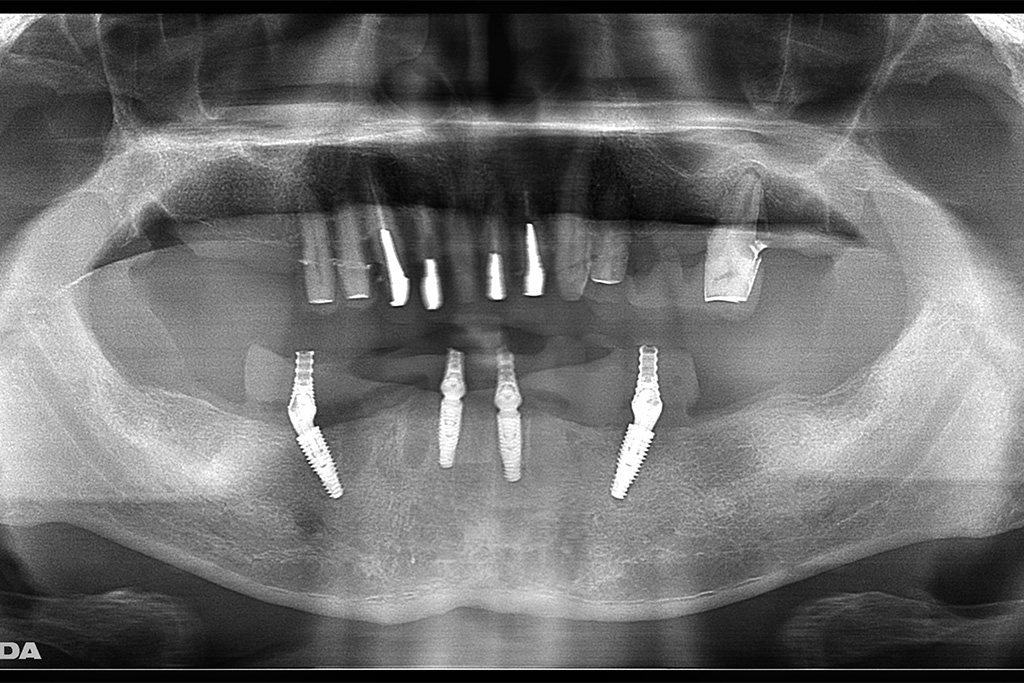

父のレントゲン写真と口腔内を見て、インプラントを入れる位置を一緒に決めて行きました。

その右上は骨がないためサイナスリフトという処置を施した後にインプラントを入れる手術をしなければならないのですが、(サイナスリフトは骨を作るだけで6ヶ月待ちます。)

私は水口先生が開発したオステオプッシャーを用いて、骨がないところに骨を足す手術と並行してインプラントを入れる手術を施しました。

左側の入れ歯を入れていたと言っている場所には通常の方法でインプラント治療を、左上の奥歯2本は歯周病でグラグラだったため抜歯と同時にインプラントと治療を行いました。

左側のレントゲンがが最初の状態です。右側がインプラントを入れ、被せ物まで入れた状態のレントゲンです。